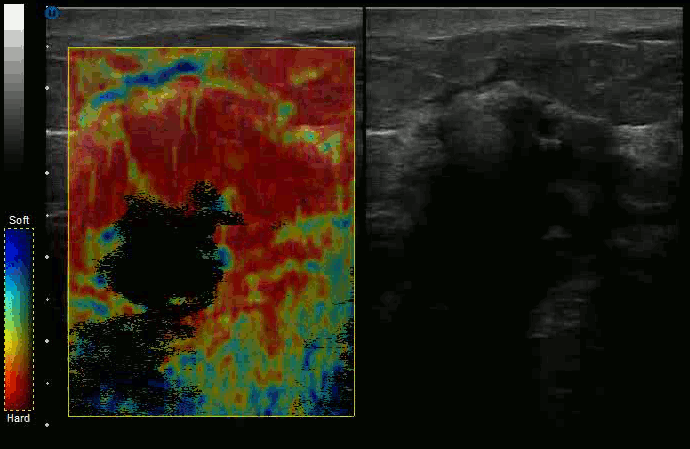

준정적 탄성 영상(과거의 이유로 단순히 '탄성 영상'이라고 불리기도 함)은 가장 초기의 탄성 영상 기술 중 하나이다. 이 기술에서는 조직에 외부 압력을 가하고, 압박 전후의 초음파 영상을 비교한다. 가장 적게 변형된 이미지 영역이 가장 단단하고, 가장 많이 변형된 영역이 가장 덜 단단하다.[2] 일반적으로, 작업자에게 표시되는 것은 상대적인 왜곡(변형률)의 이미지이며, 이는 종종 임상적으로 유용하다.[3]

전단파 탄성 영상(SWEI)은 음향 방사력을 이용하여 조직 깊숙한 곳에 '밀기'를 유도한다. 이 밀기로 인해 발생하는 교란은 전단파 형태로 조직을 통해 측면으로 이동한다. 초음파나 MRI 같은 영상 방식을 사용하여 파동이 다양한 위치에 도달하는 속도를 관찰함으로써, 조직의 강성을 추론할 수 있다. "탄성 영상"과 "탄성계측법"은 같은 의미이므로, 전단파를 이용해 탄성 맵을 나타내는 SWEI라는 용어는 종종 SWE로 대체된다.SWEI와 ARFI의 주요 차이점은 SWEI는 빔 축에서 측면으로 전파되는 전단파를 이용하여 탄성 맵을 생성하는 반면, ARFI는 밀기 빔의 축에서 탄성 정보를 얻고 여러 번의 밀기를 통해 2차원 강성 맵을 생성한다는 것이다.[7] ARFI에는 전단파가 관여하지 않으며, SWEI에는 축 방향 탄성 평가가 없다. SWEI는 초음속 전단 영상(SSI)에서 구현된다.

수퍼소닉 전단 영상은 유방, 갑상선, 간, 전립선 및 근골격계 영상에서 유용하다는 보고가 있다.[46][47][48]

초음속 전단파 영상(SSI)은 조직 강성의 정량적이고 실시간적인 2차원 지도를 제공한다.[8][9] SSI는 SWEI를 기반으로 하며, 음향 방사력을 사용하여 관심 조직 내부에 '밀기'를 유도하여 전단파를 생성하고, 결과적인 전단파가 조직을 얼마나 빠르게 통과하는지로부터 조직의 강성을 계산한다. 국소 조직 속도 지도는 기존의 스펙클 추적 기술로 얻으며, 조직을 통과하는 전단파 전파의 전체 동영상을 제공한다. SSI에는 두 가지 주요 혁신이 있다. 첫째, SSI는 여러 번의 거의 동시적인 밀기를 사용하여 초음속으로 매체를 통과하는 전단파의 원천을 생성한다. 둘째, 생성된 전단파는 초고속 영상 기술을 사용하여 시각화된다. 역 알고리즘을 사용하여 매체의 전단 탄성은 파동 전파 동영상으로부터 정량적으로 매핑된다. SSI는 1초에 10,000 프레임 이상으로 깊숙한 장기를 촬영할 수 있는 최초의 초음파 영상 기술이다. SSI는 조직의 기계적 특성을 설명하는 일련의 정량적 및 생체 내 매개변수, 즉 영률, 점도, 이방성을 제공한다.이 접근 방식은 유방, 갑상선, 간, 전립선 및 근골격계 영상에서 임상적 이점을 입증했다. SSI는 여러 개의 고해상도 선형 변환기를 사용하여 유방 검사에 사용된다.[10] 대규모 다기관 유방 영상 연구에서 전단파 탄성 영상이 표준 B-모드 및 컬러 모드 초음파 영상의 해석에 추가될 때 유방 병변의 분류[12]에서 재현성[11]과 상당한 개선이 모두 입증되었다.